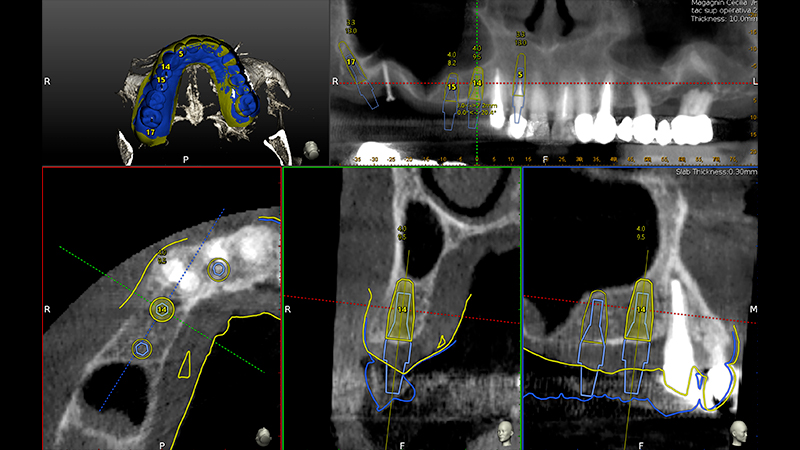

Veniva eseguita la pianificazione del caso con l'utilizzo dell'STL della Biocopia (Fig. 9) e della gengiva guarita (Fig. 10), e di tutti gli impianti: zona 12 con pianificazione post-estrattiva flapless con Socket Shield (Fig. 11), zona 14 (Fig. 12), zona 15 (Fig. 13) e zona pterigoidea (Fig. 14). Dopo la chirurgia (Video 1 e 2), OPT post-operatoria e endorali venivano fatte per valutare il rialzo di seno trans-crestale (Figs. 15, 16, 17, 18).

Pianificazione chirurgica della posizione implantare

Fig. 9 - Pianificazione chirurgica della posizione implantare su Software Navident (Claronav) basandosi sulla posizione dei denti originali mediante sovrapposizione di impronta ottica con e senza i denti (STL). Particolare attenzione è stata posta al parallelismo degli impianti 15 e 14, al corretto posizionamento con tecnica Socket Shield su 12 e alla correzione predefinita di 30° del moncone dell'impianto pterigoideo per mantenere il parallelismo conometrico protesico

Pianificazione chirurgica della posizione implantare su Software Navident

Fig. 10 - Pianificazione chirurgica della posizione implantare su Software Navident (Claronav) basandosi sulla posizione dei denti originali mediante sovrapposizione di impronta ottica con e senza i denti (STL). Particolare attenzione è stata posta al parallelismo degli impianti 15 e 14, al corretto posizionamento con tecnica Socket Shield su 12 e alla correzione predefinita di 30° del moncone dell'impianto pterigoideo per mantenere il parallelismo conometrico protesico

Fig. 11 - Pianificazione chirurgica della posizione implantare su Software Navident (Claronav) basandosi sulla posizione dei denti originali mediante sovrapposizione di impronta ottica con e senza i denti (STL). Particolare attenzione è stata posta al parallelismo degli impianti 15 e 14, al corretto posizionamento con tecnica Socket Shield su 12 e alla correzione predefinita di 30° del moncone dell'impianto pterigoideo per mantenere il parallelismo conometrico protesico

Fig. 12 - Pianificazione chirurgica della posizione implantare su Software Navident (Claronav) basandosi sulla posizione dei denti originali mediante sovrapposizione di impronta ottica con e senza i denti (STL). Particolare attenzione è stata posta al parallelismo degli impianti 15 e 14, al corretto posizionamento con tecnica Socket Shield su 12 e alla correzione predefinita di 30° del moncone dell'impianto pterigoideo per mantenere il parallelismo conometrico protesico

Fig. 13 - Pianificazione chirurgica della posizione implantare su Software Navident (Claronav) basandosi sulla posizione dei denti originali mediante sovrapposizione di impronta ottica con e senza i denti (STL). Particolare attenzione è stata posta al parallelismo degli impianti 15 e 14, al corretto posizionamento con tecnica Socket Shield su 12 e alla correzione predefinita di 30° del moncone dell'impianto pterigoideo per mantenere il parallelismo conometrico protesico

Fig. 14 - Pianificazione chirurgica della posizione implantare su Software Navident (Claronav) basandosi sulla posizione dei denti originali mediante sovrapposizione di impronta ottica con e senza i denti (STL). Particolare attenzione è stata posta al parallelismo degli impianti 15 e 14, al corretto posizionamento con tecnica Socket Shield su 12 e alla correzione predefinita di 30° del moncone dell'impianto pterigoideo per mantenere il parallelismo conometrico protesico